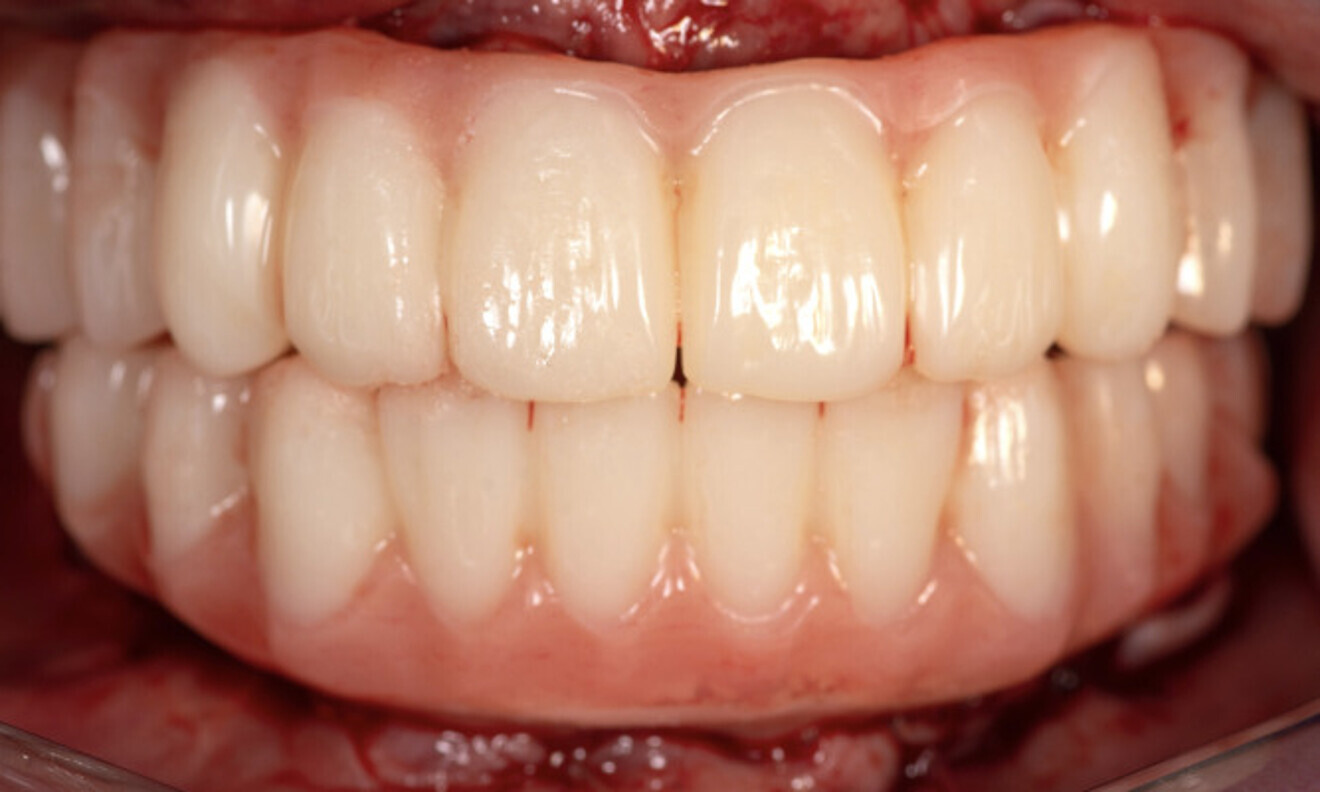

On the same day as extraction surgery, employing the principle of immediacy and without the necessity of guided bone regeneration, an outstanding functional and aesthetic outcome was accomplished with two Straumann BLX implants and two Straumann zygomatic implants in the maxilla and four Straumann BLX implants in the mandible. Six months later, the patient was very pleased with the retention and aesthetics of the final full-arch implant prostheses. The clinical and radiographic evaluation yielded stable and favourable results, indicating positive progress. The prostheses fulfilled the patient’s expectations and needs. She was delighted with the significant change in her smile and in her quality of life (Figs. 16 & 17).

Fig. 16

Fig. 17